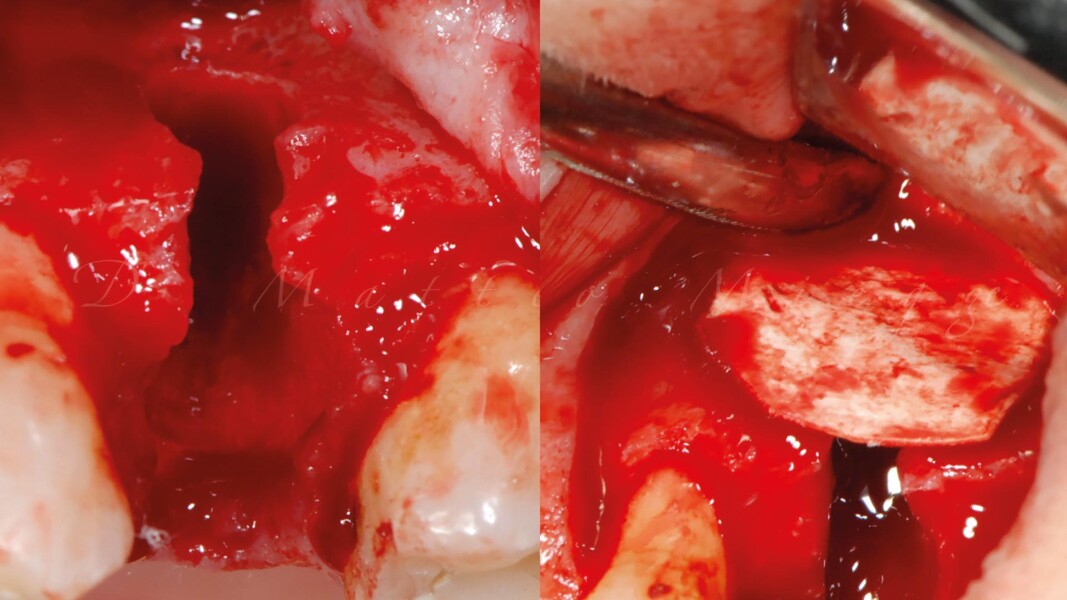

Una paziente di 50 anni presentava un premolare superiore non recuperabile. Dopo CBCT preoperatoria (T0) (Fig. 1), si è proceduto all’estrazione atraumatica e alla gestione dell’alveolo mediante posizionamento vestibolare di una membrana corticale eterologa (Lamina fine 0,7 mm, 35 × 15 mm, OsteoBiol) e riempimento con spugne di collagene (Figg. 2, 3). Sono stati applicati punti di sutura in nylon non riassorbibile 4/0. Dopo sei mesi di guarigione, una nuova CBCT (T1) ha consentito la valutazione della qualità ossea. Per la fase implantare è stato eseguito un lembo secondo la tecnica del roll flap, con preservazione delle papille interdentali e aumento del tessuto cheratinizzato (Fig. 4). È stato inserito un impianto JD Evolution Plus (4,3 × 11,5 mm) ottenendo un’eccellente stabilità primaria. Durante la chirurgia è stato prelevato un campione osseo per analisi istologica (Fig. 5).  Il lembo è stato suturato con nylon 4/0 intorno all’abutment di guarigione. Dopo due mesi, la paziente è stata riabilitata con una corona monolitica in zirconia realizzata da impronta digitale intraorale (Fig. 6).

Il protocollo chirurgico ha seguito i principi della tecnica LAR, prevedendo una gestione stratificata dei materiali rigenerativi al fine di ottenere stabilità volumetrica e controllo biologico del sito post-estrattivo. La membrana ossea eterologa ha fornito un supporto rigido e stabile per la rigenerazione ossea e il mantenimento dei contorni alveolari. Le spugne di collagene sono state scelte per la loro biocompatibilità e capacità di favorire emostasi e rigenerazione tissutale. Le misurazioni dello spessore osseo sono state effettuate su CBCT a T0 e T1 in tre punti: